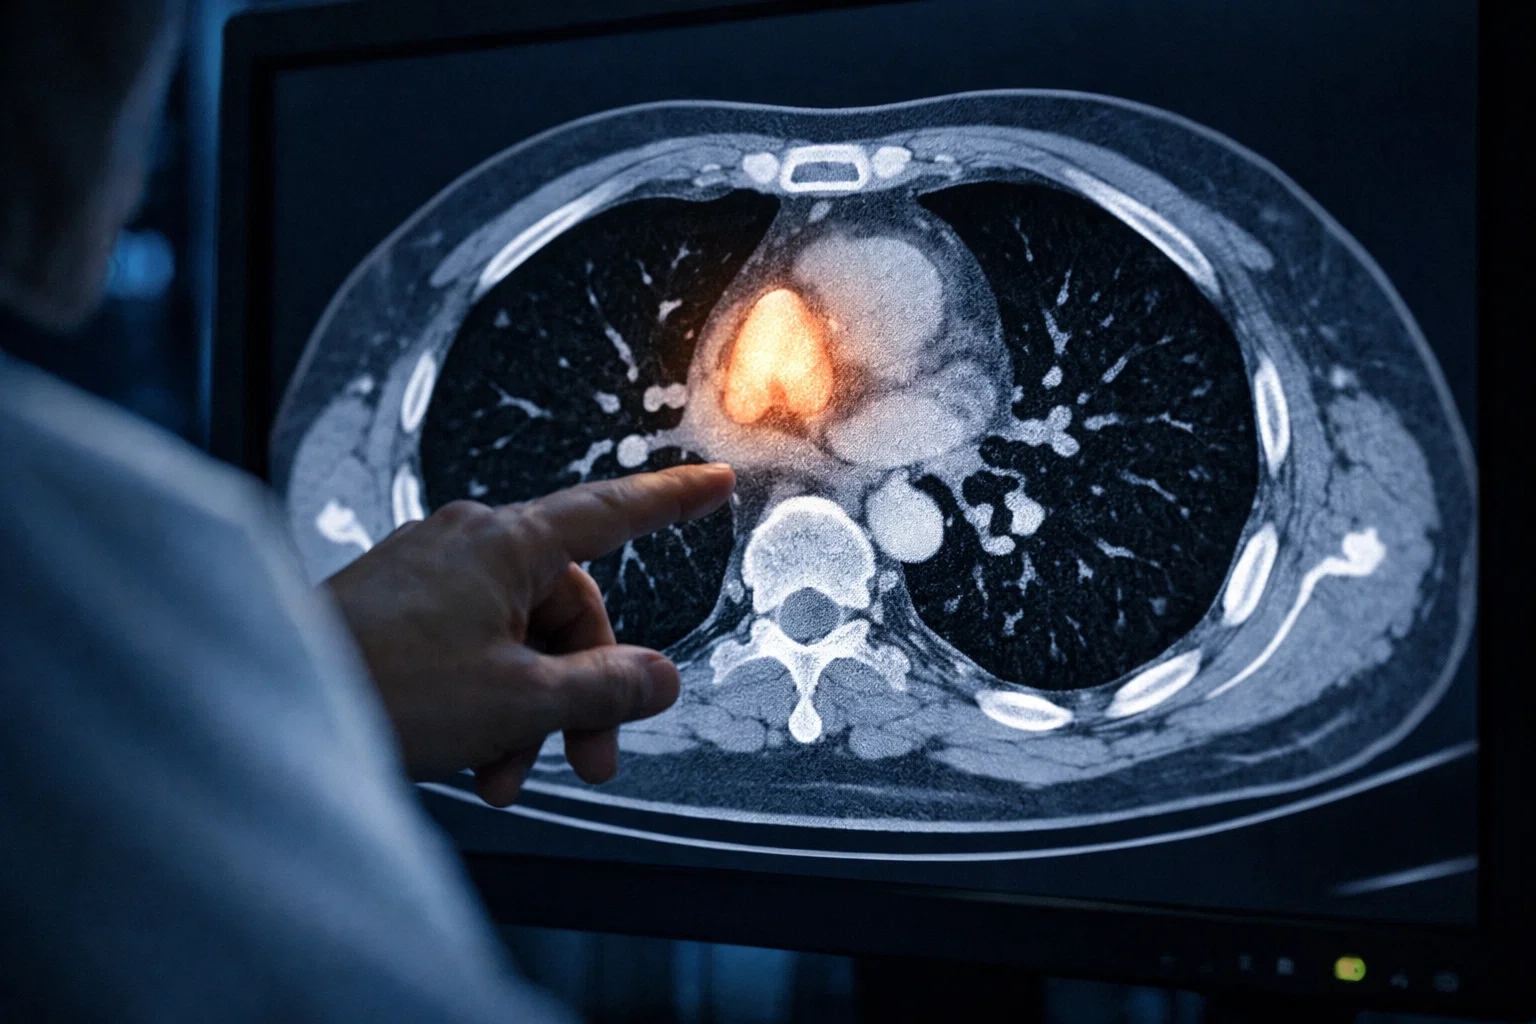

Yapay Zeka Timus Sağlığını Nasıl Ölçtü?

Araştırmacılar, binlerce kişinin BT taramalarını analiz eden bir yapay zeka modeli geliştirdi. Bu sistem, timusun yapısını ve dokusunu inceleyerek kişiye özel bir "timus sağlığı puanı" oluşturdu. Geniş ölçekli veri analizi sayesinde timusun görünmeyen etkileri ilk kez bu kadar net ölçülebildi. Çalışma, 25 binden fazla kişi üzerinde yürütüldü ve geniş ölçekli veri ile desteklendi.